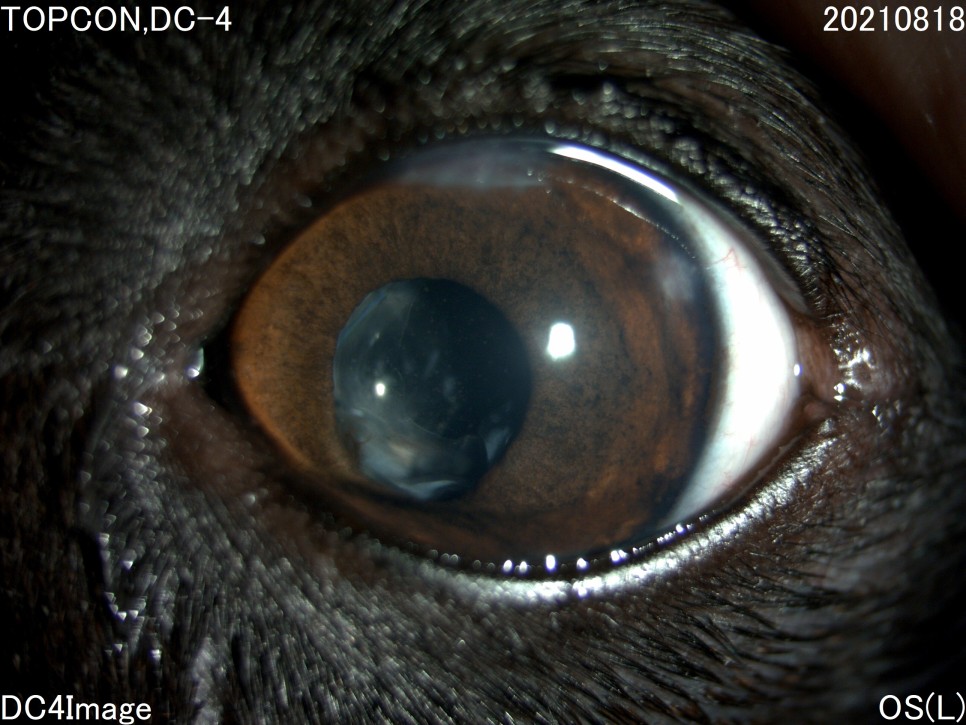

수술 일주일 후

수술 후 사진에 보이는 하얀 것은 무엇입니까?위의 사진상, 동공내에 보이는 흰 부분은 「후낭 백탁」이라고 하는 증상과 백내장에 의한 수정체 낭의 섬유화입니다.문자 그대로 백내장 수술 후 수정체의 후낭이라는 부분에 백탁 현상이 생기고, 이는 수정체 전낭 세포의 이주 등에 의해 발생합니다. 완성도는 아이에 따라 다르며, 개의 백내장 수술 후 80%이상에서 볼 수 있습니다.

인간의 경우 레이저로 후낭을 절제하는 시술 등을 하고 있는데, 강아지, 고양이의 경우 이러한 레이저 시술 후 합병증 발생률이 크기 때문에 후낭 백탁으로 인한 시력저하가 심하지 않는 한 별다른 처치를 하지 않고 있습니다.